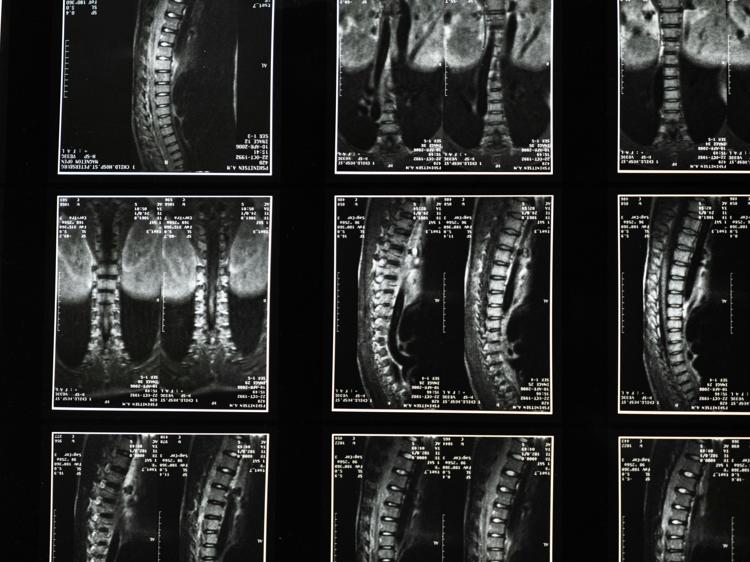

脊髓炎是一种累及脊髓的神经系统疾病,西医一般会针对病因采取规范治疗,而中医则从整体观出发,通过调节身体机能、改善内环境来辅助促进恢复,两者结合能更好地帮患者应对疾病。不少人对中医调理脊髓炎的具体方法有疑问——比如中药是不是随便吃补药就行?针灸有没有副作用?今天就从核心逻辑到实际操作,详细拆解中医辅助调理脊髓炎的关键内容。